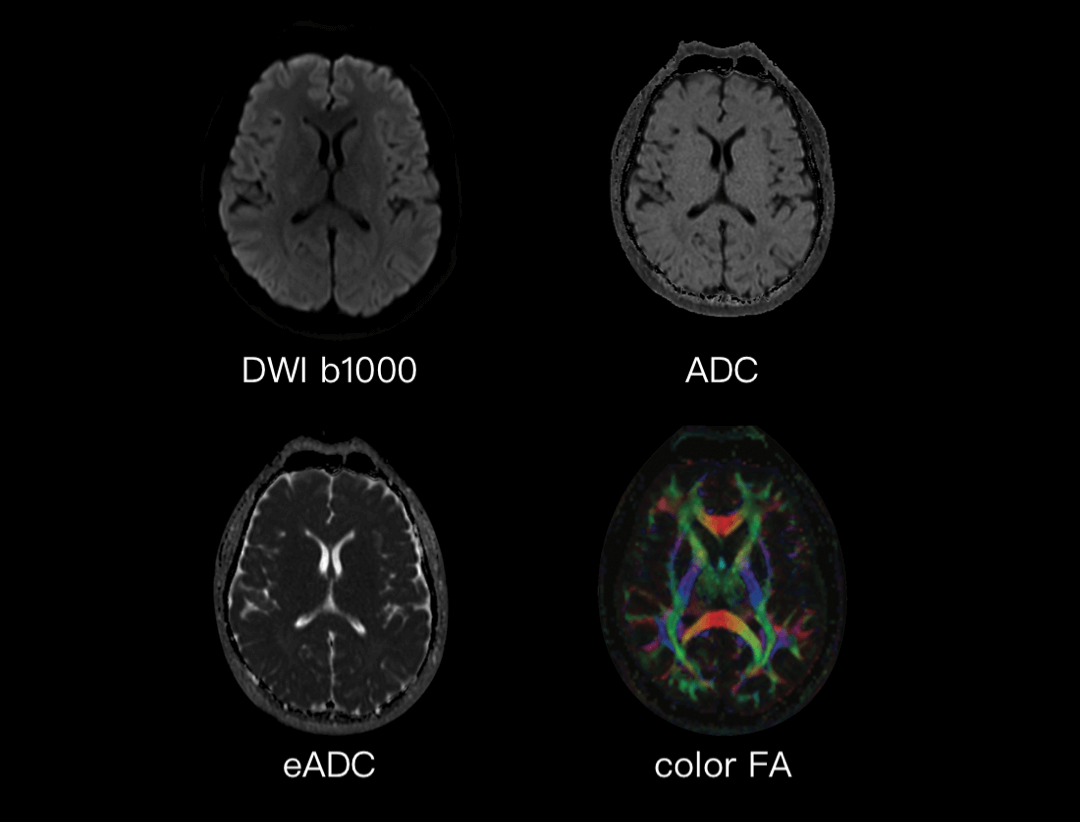

多参数神经成像

提供FA,RA,ADC,Color FA等参数图,能够反映组织内水的运动速度和方向,为疾病诊断,例如脑白质病变提供精准信息。